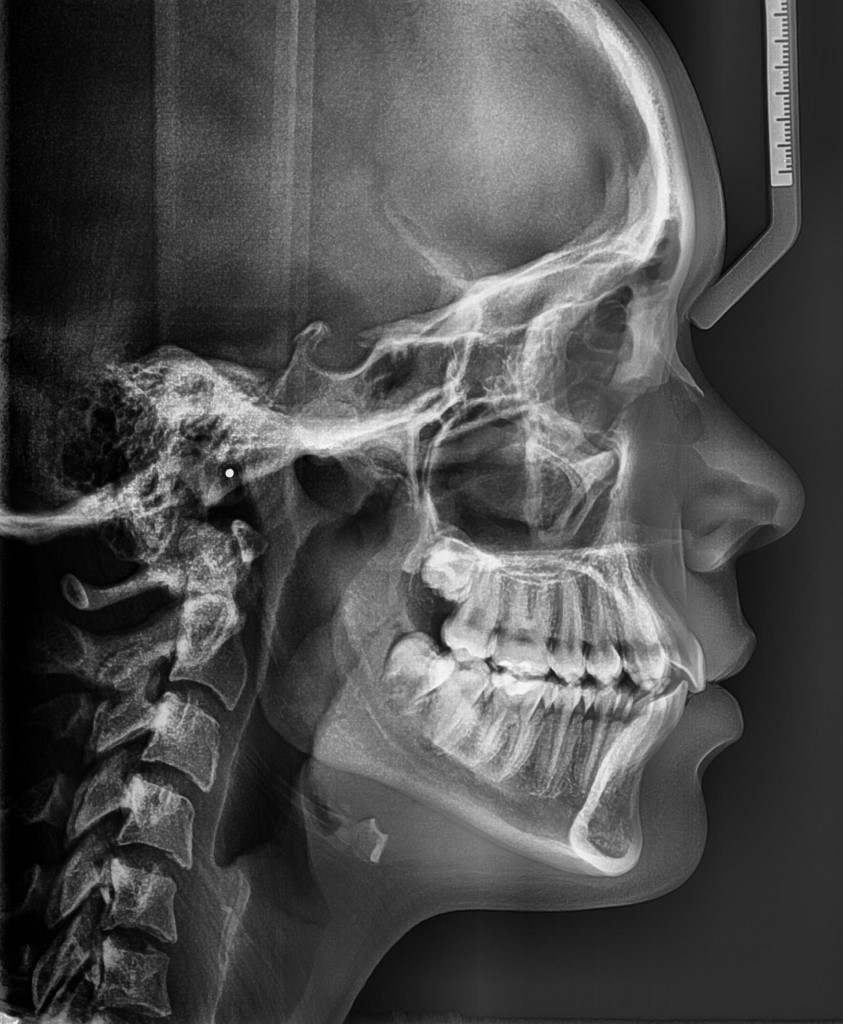

Ofrecemos la más alta tecnología con una atención profesional y personalizada por parte del equipo altamente calificado en donde contará con el mejor estudio para sus pacientes.